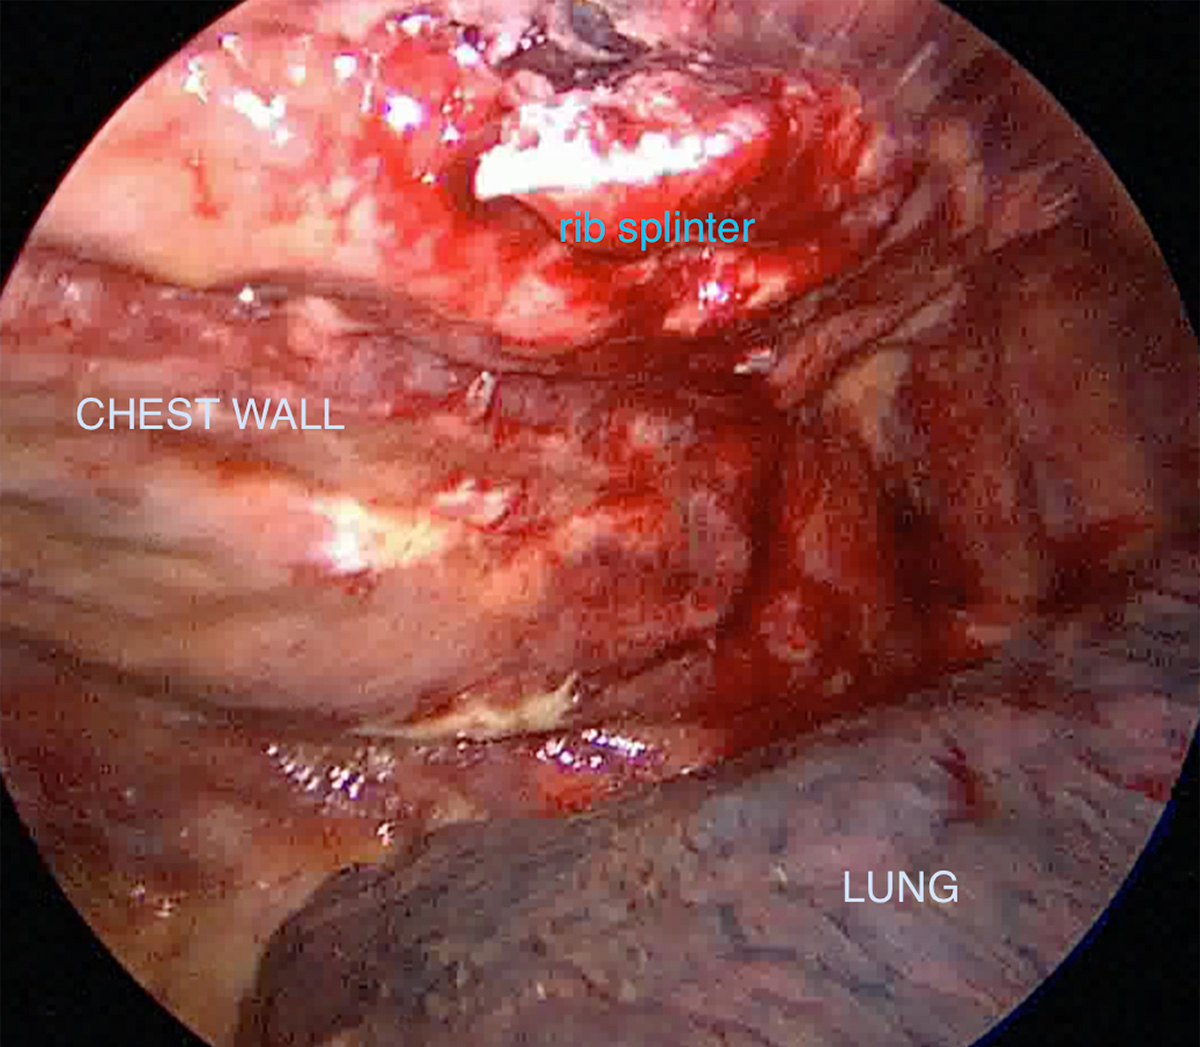

The rib injury is assessed internally as its often easier to see actually where the ribs are broken and how badly they are broken, and the exact location is marked prior to performing a small incision over the broken ribs.

Assessment of rib injury infernally using a keyhole approach showing a rib fracture with a sharp splinter of rib in chest cavity.